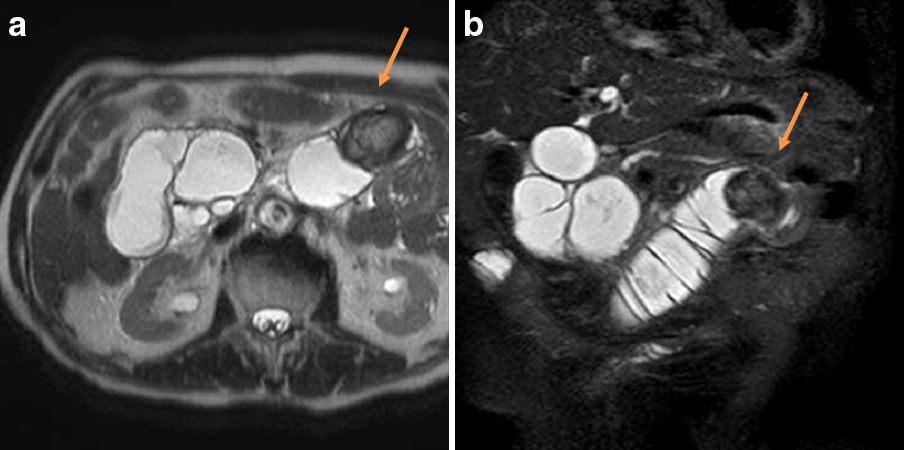

腹部MRI所見:T2強調画像では,Y脚内に周囲がやや低信号で中心が高信号の類円形の構造物を認め,結石の存在が示唆された(Fig. 3a, b).結石はCT撮像時からの時間経過に伴い肛門側へ移動していた.

Abdominal T2-weighted MRI image showed a round structure with low signal intensity on the lateral side and high signal intensity on the internal side at the site of the Roux-en-Y anastomosis (a, b).